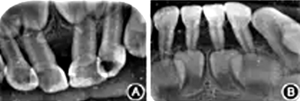

輔助檢查:基因檢測患者基因組ELANE基因有1個(gè)雜合突變(c.640G>A ),父母及其兄均未檢測到此突變,此突變?yōu)樽园l(fā)突變;血常規(guī):紅細(xì)胞3.13 × 1012/L,白細(xì)胞4.22 × 109/L,中性粒細(xì)胞絕對(duì)值0.48 × 109/L,血小板330×109/L,血紅蛋白83 g/L,C反應(yīng)蛋白>200 mg/L,超敏C反應(yīng)蛋白>5.0 mg/L??谇籜線片示牙槽骨呈廣泛性吸收達(dá)根中及牙尖1/3,遠(yuǎn)中切角缺損,牙冠可見低密度影像(圖2)。

圖2 重型先天性中性粒細(xì)胞缺乏癥患者前牙X線片示牙槽骨廣泛性吸收

A:上頜前牙;B:下頜前牙